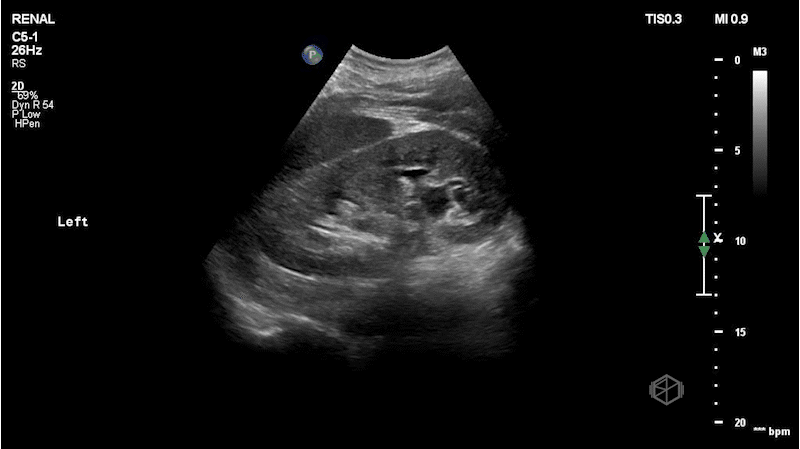

As you know, during the holidays, delivery drivers work extremely hard to get our packages to us as quickly as possible. Dr. Mendelow scanned a middle-aged delivery man with left flank pain that came on suddenly while he was out delivering holiday packages. The right kidney was normal. He obtained the following images:

This patient has mild-to-moderate left hydronephrosis with an approximately 5mm ureteropelvic junction (UPJ) stone. Note the hyperechoic stone with shadowing posterior to it just outside the kidney in image 4 and in clip 2. The patient later had a CT that demonstrated the same but the stone had moved just slightly lower into the proximal ureter.

Diagnosis: Left mild-to-moderate hydronephrosis with a UPJ stone